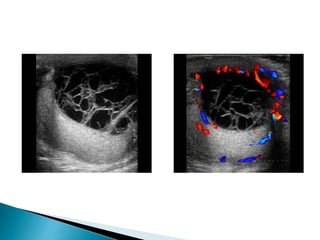

 In the acute phase ultrasound show testicular

swelling with patchy or diffuse reduction in

echogenicity.

 Doppler ultrasound show increased

vascularity

 On ultrasound the epididymis shows swelling,

 Diffuse or patchy reduction in echogenicity,

 Doppler ultrasound demonstrates

hypervascularity.